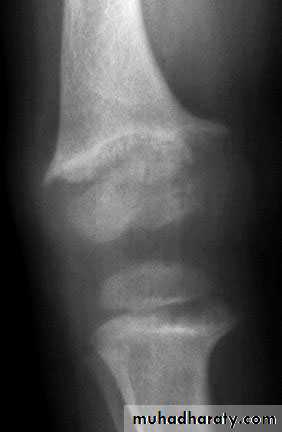

Clavicuiar lysis, Subperiosteal resorption

Brown tumors ,General osteopenia

(Bone resorption is virtually pathognomonic(Subperiosteal resorption

Radial aspect of middle phalanges

(especially index and middle finger)

Phalangeal tufts

Trabecular resorption

Brown tumors (cystlike lesions) may be found anywhere in the skeleton but

especially in the pelvis, jaw, and femur.